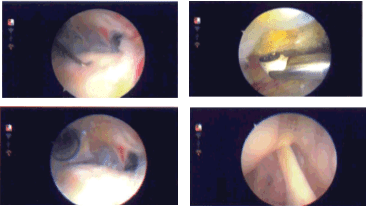

Examination of the rotator cuff showed partial bursal-sided tearing, which was cleaned with the use of a shaver. No attempt was made to repair the rotator cuff. The acromial impingement was removed by performing an acromioplasty with the use of coblation wand followed by a burr removing the acromial spur as well as using the coracoacromial ligament. The AC joint did not show any arthritic changes and no excision was done. The final pictures were taken and saved.

Intraoperative Arthroscopy Images